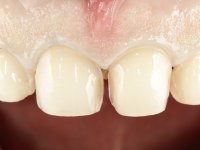

Realizado o diagnóstico e tomada a decisão quanto ao tratamento a executar, tornou-se importante definir qual a sequência de trabalho a adotar no sentido de conseguir a reabilitação da D.V.O. (V.D.O), de forma progressiva e equilibrada. Na primeira fase fez-se uma pré-impressão da arcada inferior com silicone tipo “putty” e em seguida realizou-se o preparo dentário de todo o sector posterior. O preparo para os overlays foi feito coronalmente à linha amelo cementaria no sentido de ser o mais conservador possível. A impressão foi feita com técnica de dupla mistura após afastamento gengival realizado com pasta de caulino. A provisória foi realizada com resina composta de polimerização dual. Em laboratório foram realizados os overlays após se ter aberto ligeiramente (1,5mm) a D.V.O. nos modelos montados em articulador semi-ajustável. Simultaneamente o sector antero-inferior foi encerado no sentido de acompanhar este aumento da D.V.O. Também foi confecionada uma chave de silicone translucido para posterior confeção dos provisórios antero-inferiores. Em boca foi primeiro realizada a provisionalização dos dentes anteriores utilizando resina composta previamente aquecida após preparação das superfícies dentárias para a adesão. Foi colocado o dique de borracha para promover o isolamento absoluto e posteriormente foram colados os overlays. Em laboratório foi realizada nova chave de silicone para confecionar os provisórios antero-superiores. Seguidamente em boca foram preparados os seis dentes antero-superiores após colocação do fio de afastamento gengival. Feita a preparação adequada das superfícies dentárias foi realizada a impressão com técnica de dupla mistura e a respetiva provisória. Em laboratório foram confecionadas 6 facetas feldespáticas num modelo de trabalho tipo “Geller”. A provisória foi removida e as facetas foram coladas em boca utilizando um isolamento relativo competente. Esta opção foi tomada em virtude de uma prévia experiencia negativa com a colocação do dique de borracha na mandibula. Após a colagem dos laminados antero-superiores foram dadas 12 semanas para avaliar a adaptação do paciente à nova situação e então iniciar a confeção das facetas antero-inferiores. Após colocação do fio de afastamento gengival. foram feitos os preparos dentários adequados e em seguida foi feita a impressão. Também foi feita a preparação do dente 3.4 que, entretanto, tinha sofrido uma fratura do overlay. As facetas e a restauração do 3.4 foram realizadas num modelo de trabalho tipo “Geller”. Após remoção da provisória, as facetas foram coladas em boca, utilizando um isolamento relativo pelas razões apontadas anteriormente. Após colocação do trabalho o paciente foi reabilitado por outros colegas com um implante na zona do 2.6 e substituição da coroa aparafusada sobre o implante colocado no local do 3.5. Posteriormente surgiram fraturas nos overlays dos dentes 4.7 e 3.7 que foram reabilitados com overlays em Zr.